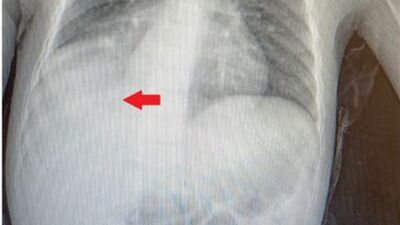

Başakşehir Çam ve Sakura Şehir Hastanesi Çocuk Cerrahi Kliniği’nden Opr. Dr. Mehmet Çakmak, "Acil servisteki doktor arkadaşlarımızın muayenesi sonrası çekilen akciğer röntgeninde, sağ alt bölgede sıvı birikimi nedeniyle bize danıştılar. Hastanın öyküsünü annesinden tekrar dinlediğimizde, şikayetlerinin 1 yaşında kardeşleriyle otururken karpuz çekirdeğini ağzına götürmesi sonrası başladığını öğrendik. O zaman çekilen akciğer röntgeninde herhangi bir patolojik bulguya rastlanmayınca, 3 yıl boyunca semptomlarının ara ara iyileşmesi nedeniyle de daha çok astım, bronşit pnömoni gibi teşhisler düşünülmüş ve buna yönelik tedaviler verilmiş. Çünkü normalde yabancı cisim aspirasyonlarında, semptomlar gerilemez. Biz, annesinin verdiği öyküyü dinleyince tomografi çektik ve sağ akciğer alt bölgeyi havalandıran bronşun, bir yabancı cisimle tıkalı olduğunu tespit ettik. Yaptığımız bronkoskopide bir karpuz çekirdeğine rastladık ve işlem esnasında karpuz çekirdeğini çıkardık" dedi.

Dr. Çakmak, kendilerini en çok, bu kadar uzun süre geçmiş olmasına rağmen karpuz çekirdeğinin nefes borusunda mukoza tabakasının içine gömülmeden kalabilmiş olmasının şaşırttığına değinerek sözlerini şöyle sürdürdü: "Çünkü üzerinden uzun süre geçmiş yabancı cisim aspirasyonlarında, vücut bir nevi kamufle edebilmek adına, yabancı cismin mukoza tabakasının altına gömülmesine sebep olur. O bölgedeki akciğer lobu atelektazi dediğimiz çökmeye doğru ilerlemişti. Eğer cismi çıkarmasaydık, o akciğer lobu tamamen söner ve kullanılamaz hale gelirdi. Biz yabancı cisim aspirasyonlarında en çok kuruyemiş ve fındık çıkarıyoruz. Kuruyemişlerin yüzde 70-80'ini fındık oluşturuyor. Bronkoskopide bizi en fazla zorlayan yabancı cisim ise leblebi tarzı şişen ve ilerleyici tıkanıklığa sebep olan kuruyemişler. Bunlar kolaylıkla parçalanıyor, soluk borusuyla akciğerin çeşitli dallarına yayılabiliyor. O da işlemin uzamasına sebep oluyor. Bir hastamızın sağ soluk borusundan iki tane beton çivisi çıkarmıştık. Yine yakalara takılan çengelli iğnelerin aspirasyonu oldukça riskli. Ayrıca toplumumuzda yaygın olarak kullanılan ve diş ağrısını geçireceğine inanılan kehribar kolyesi de bebekler için oldukça tehlikeli. Biz, Çam ve Sakura Çocuk Cerrahisi Kliniği olarak Avrupa yakasında oldukça fazla hastaya bronkoskopi yapıyoruz. Çeşitli kongrelerde de yayınladığımız çalışmalarda, aile öyküsünde yabancı cisim aspirasyonu şüpheli hastaların yaklaşık yüzde 90'ında sonuç pozitif çıkıyor. O nedenle ailenin dikkati burada çok önemli."